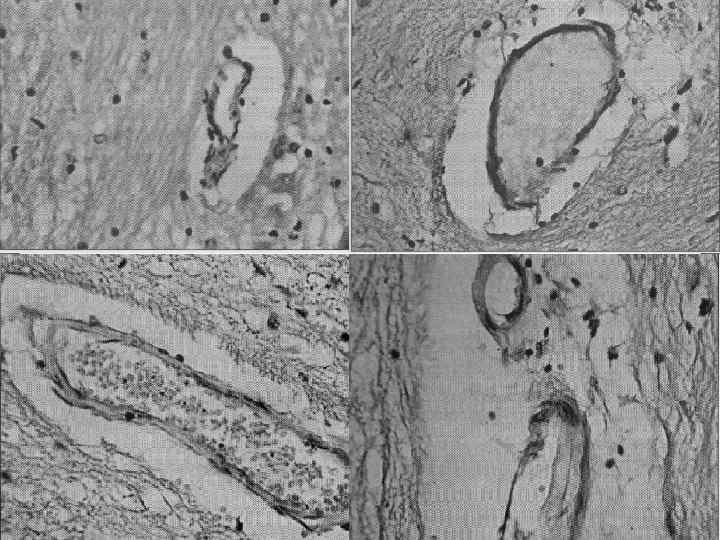

Патоморфология ДЭ Диффузная альтерация базальных мембран и эндотелия сосудов микроциркуляторного русла белого и серого вещества Повышение плотности капиллярной сети в коре лобных, височных и теменных долей Десквамация эндотелия артерий, вен мелкого калибра и венул ствола головного мозга, их спазмирование, периваскулярный отек артериол Нарушение синтеза ДНК в ядрах эндотелиальных клеток Прогрессирование эндотелиальной дисфункции [Пашковская Н. В. , 2008]